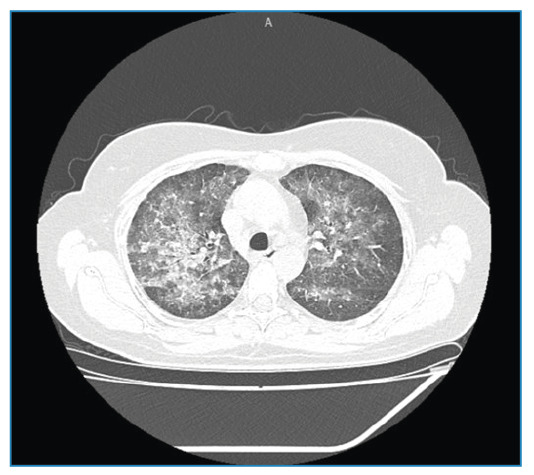

慢性基孔肯雅关节炎患者甲氨蝶呤所致肺炎。

Methotrexate-Induced Pneumonitis in a Patient with Chronic Chikungunya Arthritis.